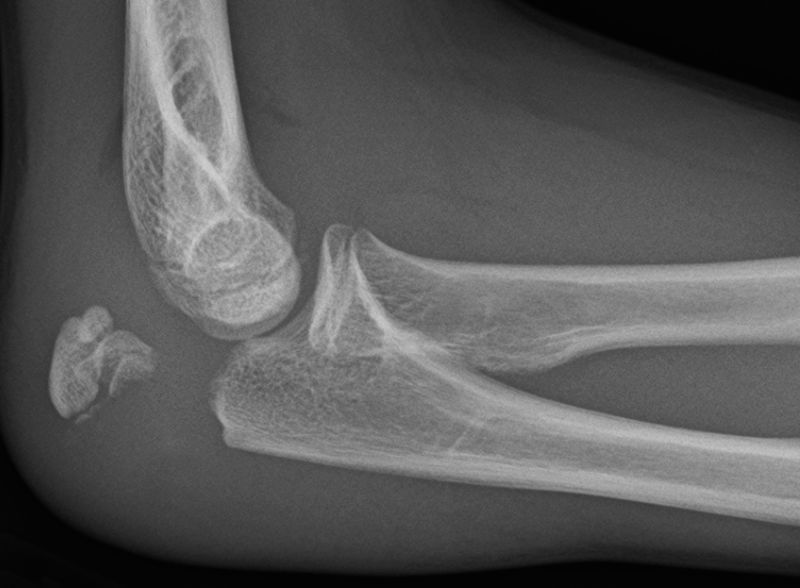

What might you see on x-ray of someone with a radial head fracture?

Sail sign (elevation of anterior fat pad)